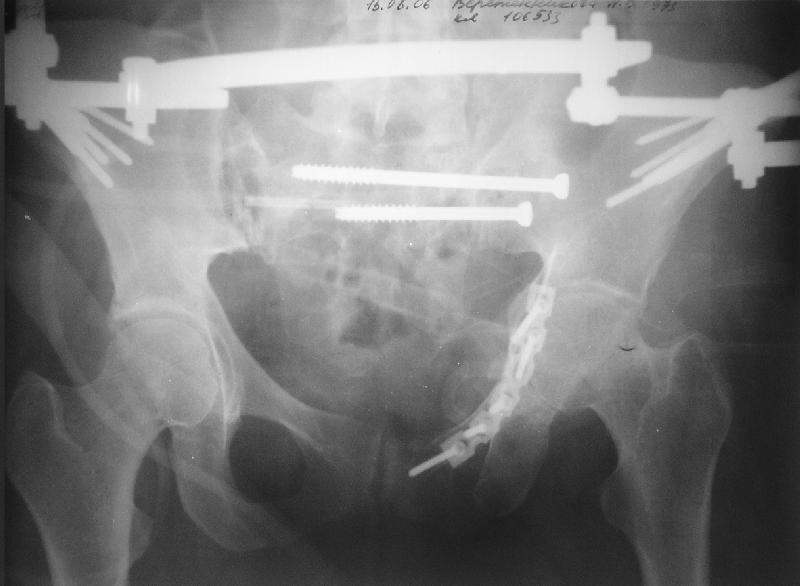

Прооперировали молодую девушку 32 лет спустя 9 мес после травмы. Имелся стойкий болевой синдром, неопороспособность левой н/конечности, моторные и сенсорные нарушения в левой голени и стопе, патологическая подвижность левой половины таза. Первым этапом закрыто в аппарате исправили деформацию ( в течении 2,5 нед). Вторым закрытое введение илиосакральных винтов в крестец (канюллированные 7,2 мм Chm) + туннелизация зоны псевдоартроза спицама Киршнера, реконструкция передних отделов таза, накостный остеосинтез . Аппарат частично демонтирпован, оставлена "передняя рама" После устранения деформации отмечен регресс неврологической симптоматики, уменьшение болевого синдрома. Интересующие вопросы: 1. Прогноз для сращения псевдоартроза крестца. 2. сроки нагрузки весом левой половины таза. Буду очень признателен за ваши мнения по этому поводу.A female 32 y.o. admitted to our unit 9 months after initial injury with pain, inability to bear weight at the left lower limb, sensor and motor disturbances in the left foot and tibia, with mobility of the left hemipelvis.At first closed reduction was performed by an external fixator within 2,5 weeks. After correction her pain decreased and some neurological progress was achieved. Now two iliosacral screws 7,2 mm were inserted, and anterior lesion was fixed by a plate. External fixator was partially unmounted, only anterior frame left in place.Images attached.How would you evaluate chances of healing of the sacrum with the current position?When would you allow weight-bearing of the left leg?THX in advance.

Мне нравится ваша закрытая репозиция девятимесячного ложного сустава, не знаю насчет туннелизации, но шурупы в 7.2 это серёзная конструкция. При стабильной фиксации крестец должен срастись, только я бы держал передний фиксатор до шести недель, костыли, а полную нагрузку разрешить через 12 недель.

При желании, передную фиксацию можно было перевести в малую нижнюю (супрацетабулярно хорошая костная масса), стержни провести через spina ilica anterior inferior в место прикрипления прямой мышцы бедра.

Нижний фиксатор немного миниатюрнее и удобнее для больной.